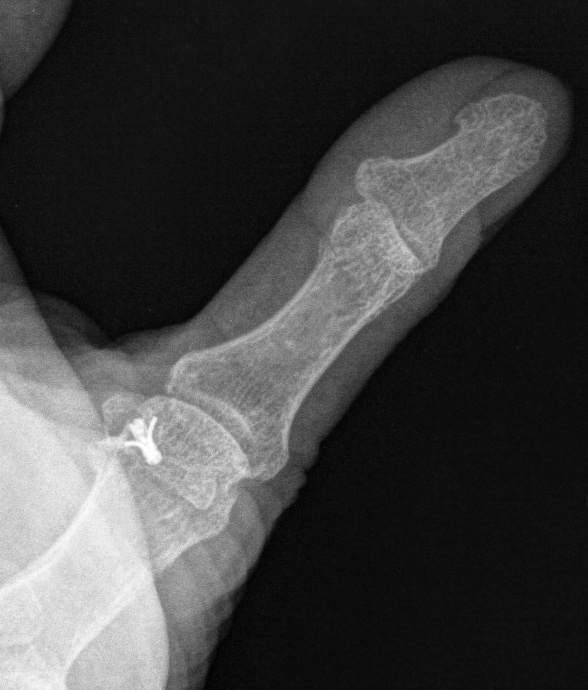

X-ray

Bony avulsion

1. Small fragment pulled away from proximal phalanx

2. Large intra-articular fracture involving >1/4 articular surface

3. Salter Harris III in pediatric population